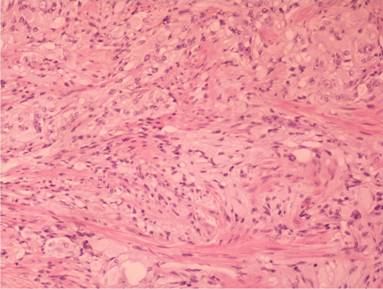

Histologically, it was located in the submucosa (Figure 5), relatively well demarcated without a capsule and with expansive pushing margins. Its stroma was extensively hyalinized. It consisted of epithelioid cells and spindle-shaped cells forming ill defined interlacing fascicles, and dispersed ganglion-like cells amongst them (Figure 6). The epithelioid cells were rather bland, arranged in alveolar, trabecular or rosettes formations, with slight nuclear pleomorphism, and sparse mitoses (less than one per 10 HPF (x200)); no necrosis was evident (Figure 7). Immunohistochemically, epithelioid cells were positive for synaptophysin and chromogranin A (Figure 8). Spindle-shaped cells and ganglion-like cells were found expressing S-100 protein (Figure 9), while epithelioid cells were negative for S-100 protein expression. Combined histopathological and immunohistochemical findings were consistent with gangliocytic paraganglioma.

Figure 6. Spindle–shaped cells with intermingled ganglion cells (H&E, x200). |

Figure 7. Epithelioid cells arranged in alveolar, trabecular or rosettes formations (H&E, x200). |